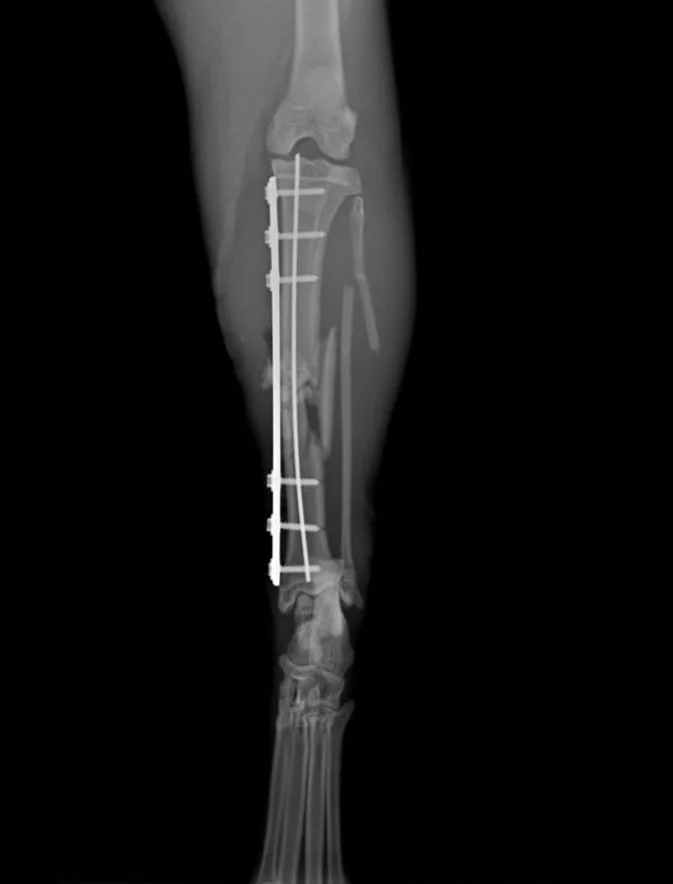

Surgery with internal fixation was performed, using a Plate and rod technique.

A Fixin V2202 1.9 locking plate was used, with 3 screws on each bone segment,

with intramedullary k-wire.

Post-op instruction consist mainly of patient confinement in a small designated area of the house (restrict jumping and running) and pain management with multimodal approach, initial follow-up radiographs are predicted to be performed at 4, 8, 12 weeks according to clinical condition of the patient.

On Follow-up at 48h, 7 and 14 days post-op owner reports good use of limb

with 1 grade lameness on the operated limb.